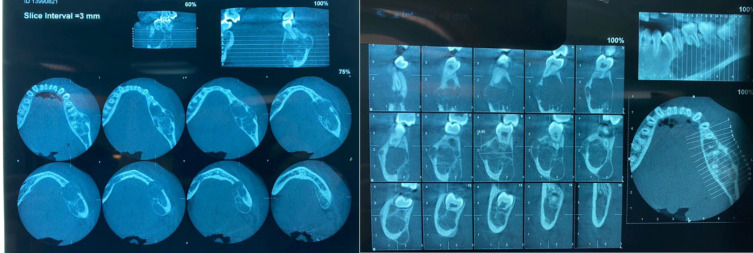

中央巨细胞肉芽肿(CGCG)是颌面部病理学领域中一种罕见但临床意义重大的疾病。本文介绍了一例令人信服的 17 岁女性中央巨细胞肉芽肿病例,揭示了该病在诊断和治疗方面遇到的挑战。鉴于 CGCG 在这一人群中的发病率相对较低,该病例不仅有助于临床对 CGCG 的理解,而且还强调了为患者量身定制特定管理策略的重要性。通过本报告,我们旨在阐明 CGCG 在表现、诊断和治疗方面的复杂性,同时强调在处理青少年患者的这一病症时必须考虑的细微因素。

The occurrence of Central Giant Cell Granuloma (CGCG) represents a rare yet clinically significant entity within the realm of maxillofacial pathology. This article presents a compelling case of CGCG in a 17-year-old female, shedding light on the diagnostic and therapeutic challenges encountered in managing this condition. Given the relative infrequency of CGCG in this demographic, the case not only contributes to the clinical understanding of CGCG but also underscores the importance of tailored, patient-specific management strategies. Through this presentation, we aim to elucidate the intricacies of CGCG manifestation, diagnosis, and treatment while highlighting the nuanced considerations essential in addressing this pathology in adolescent patients.